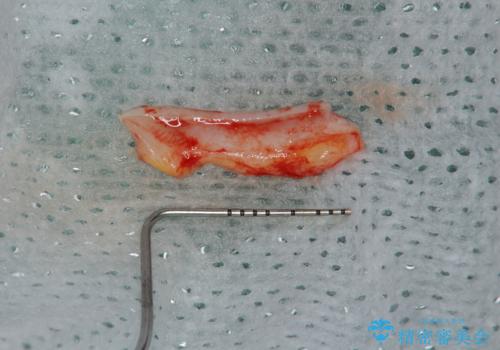

改善を図るため、結合組織移植を行い歯ぐきの再生を計画します。